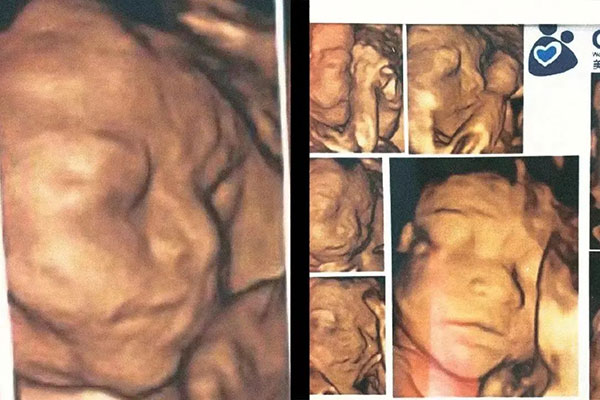

和其他CT、核磁類檢查看重儀器先進程度不同,四維B超檢查更需要醫生熟練度的操作手法以及豐富的臨床經驗,確保對疾病診斷的正確性。

我們的四維篩查,是嚴格按照國家衛生部規定的產前篩查Ⅲ級標準。

每次篩查包含40多項檢查內容,胎兒頭部、脊柱、心臟、胸腹腔臟器、四肢、臍帶、腦部等都要篩查一遍。

對于一些超聲檢查不易探查的部位,我們的醫生還會特別關注,仔仔細細地一點一點地查,并且用通俗易懂的語言解釋給孕媽聽。

為了確保數據準確,每位客人的檢查時間都有三四十分鐘。而且醫生很溫柔,操作細節也很體貼!

尤其是四維B超時,我們邀請準爸爸在安靜溫馨的B超室,一起聽胎心,一起看寶寶的小手小腳,一起拍寶寶的四維照,感受小生命的真實存在,對于準爸爸而言,小寶貝再也不是一張報告單那么單薄了。